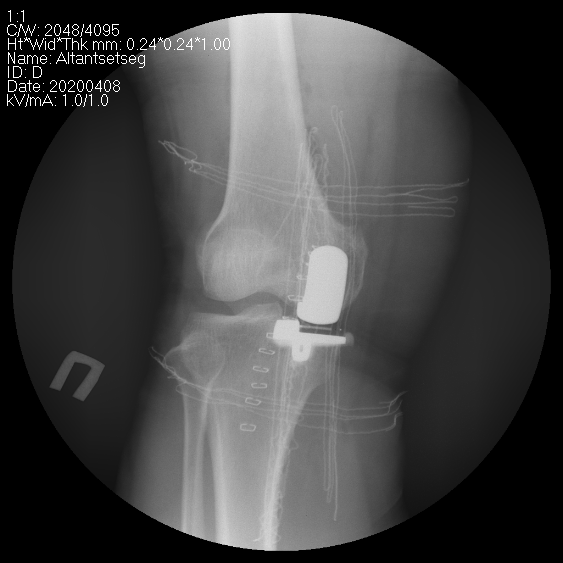

Өвдөгний үе хагас солих мэс засал (UKA) image2

Өвдөгний үеийг хэсэгчлэн солих мэс засалын төрөлд

• Дотор болон гадна булууг солих

• Тойгны үеийг солих

• Нэг талын булууг тойгны үетэй хамт солих мэс заслууд багтана.